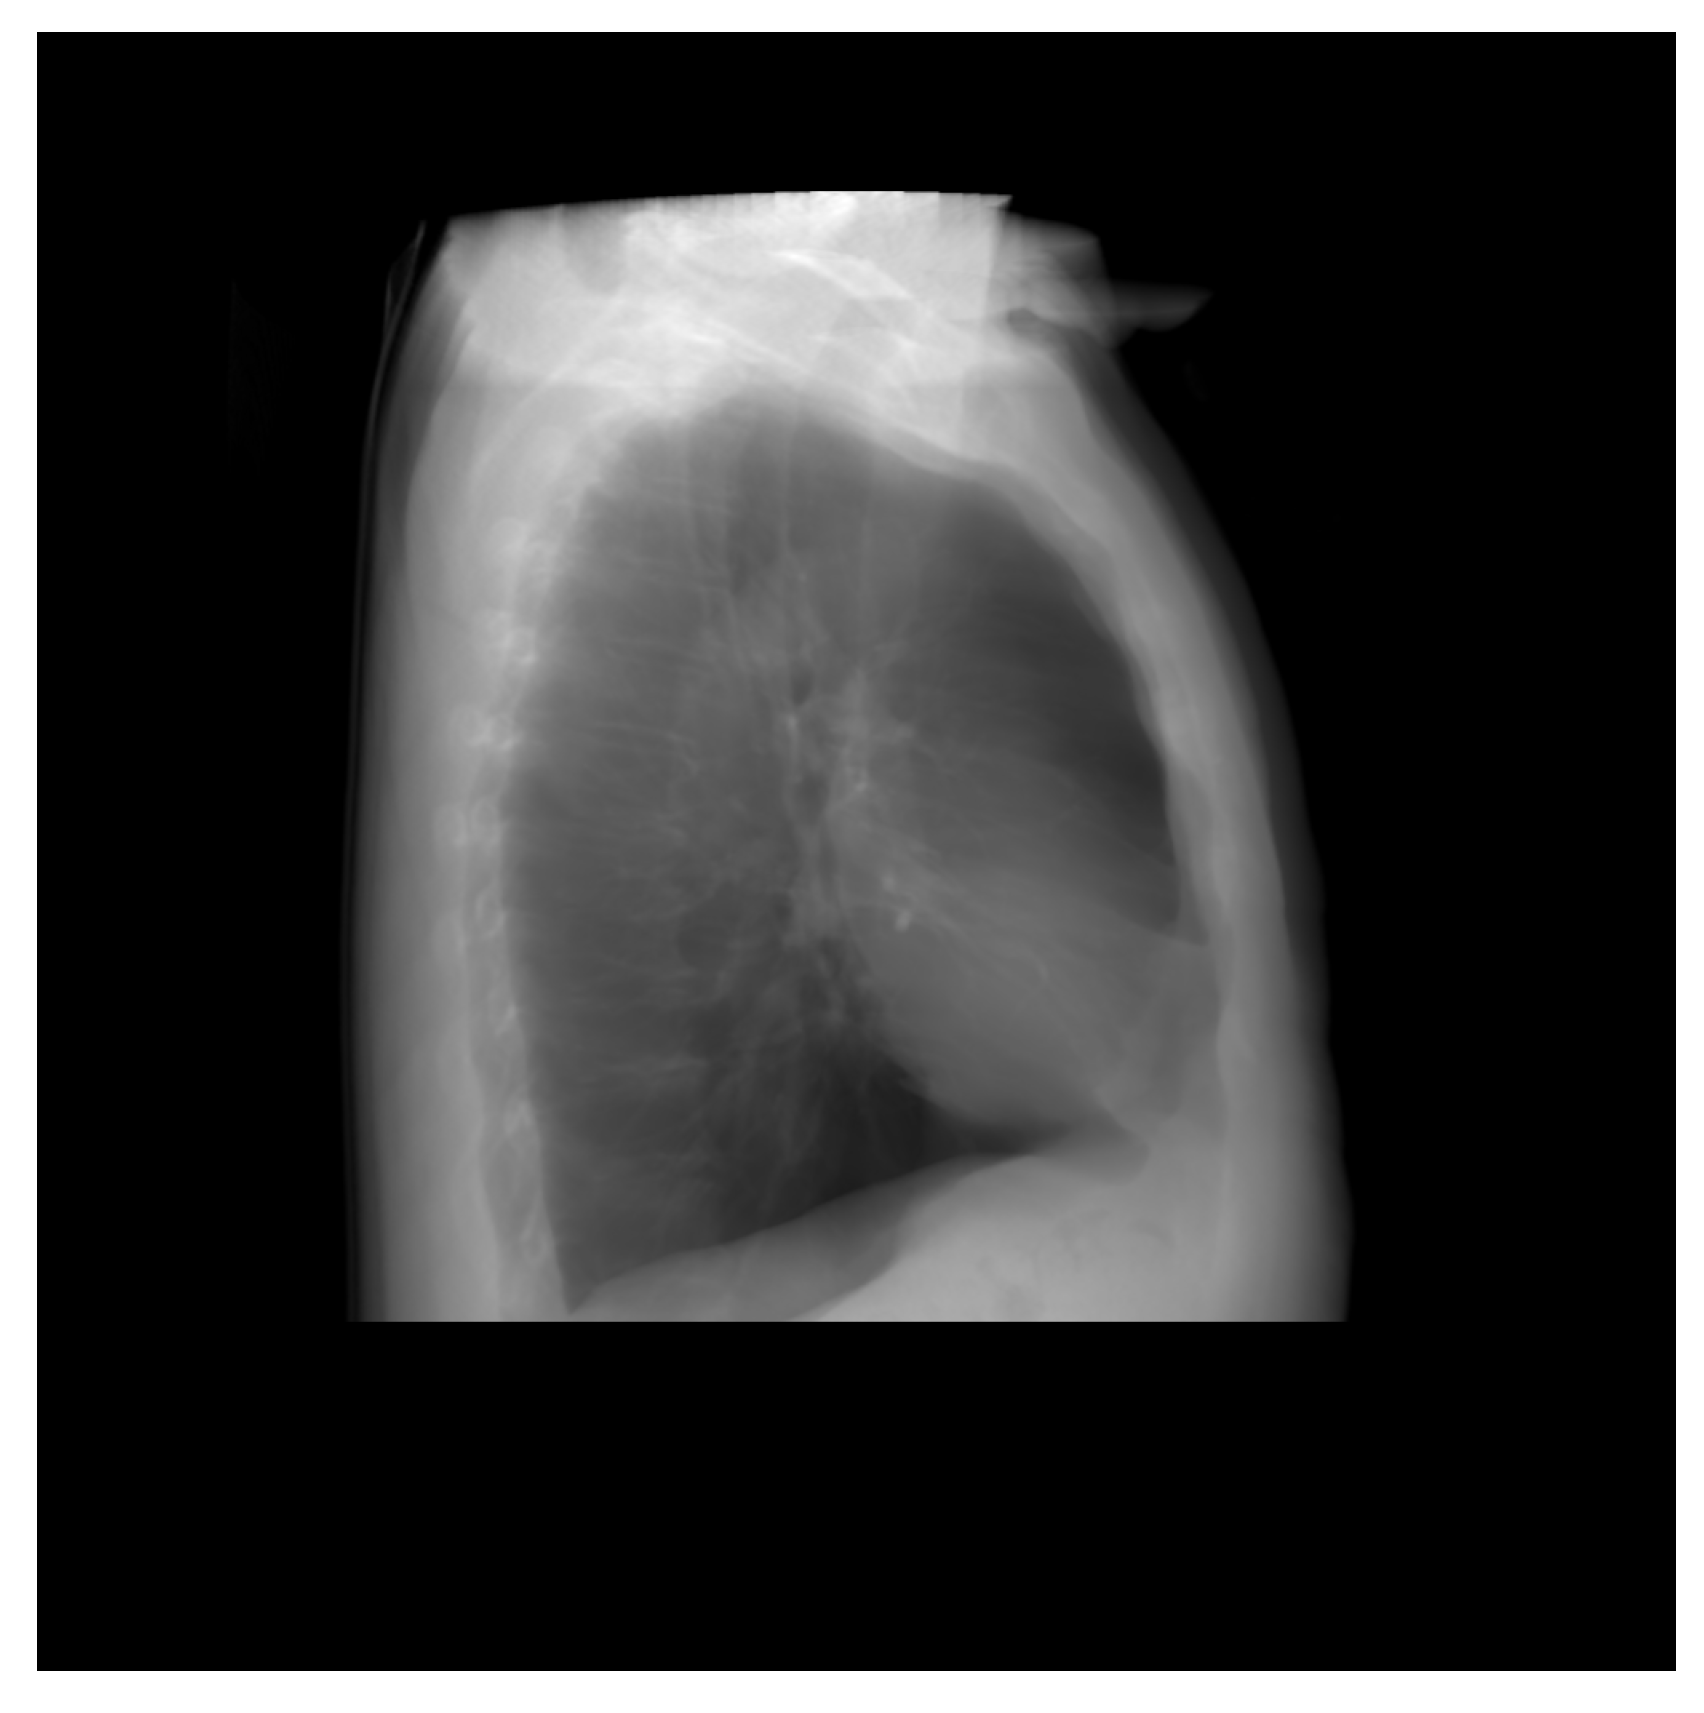

Thus, DRR is calculated by averaging the CT linear attenuation coefficient of the voxel along a ray from the virtual X-ray source to each pixel in the resultant image. DRR generation process is shown in Figure 4. However, in the segmented CT, the lung section’s CT number is 1, and 0 for the other section. Thus, averaging the intensity gives no effective result. For this, maximum intensity is considered along the ray. The Figure 5 and Figure 6 denote the PA and lateral view of the CT image respectively, and Figure 7 and Figure 8 denote corresponding segmented DRR.

Figure 5.

PA view of the DRR image.

Figure 6.

Lateral view of the DRR image.